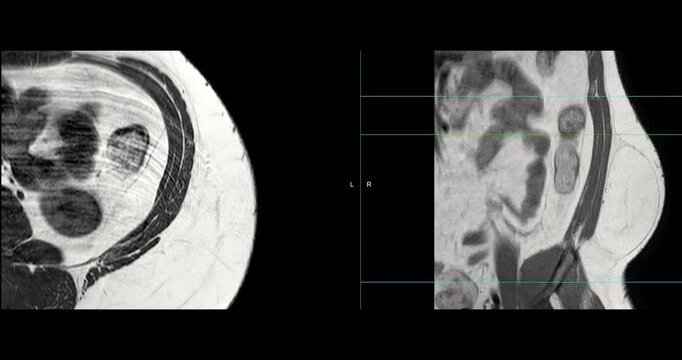

MRI whole abdomen video showing a fatty mass on the left side of the abdomen. Findings suggest a probable atypical lipomatous tumor, with differential diagnosis of well-differentiated liposarcoma.